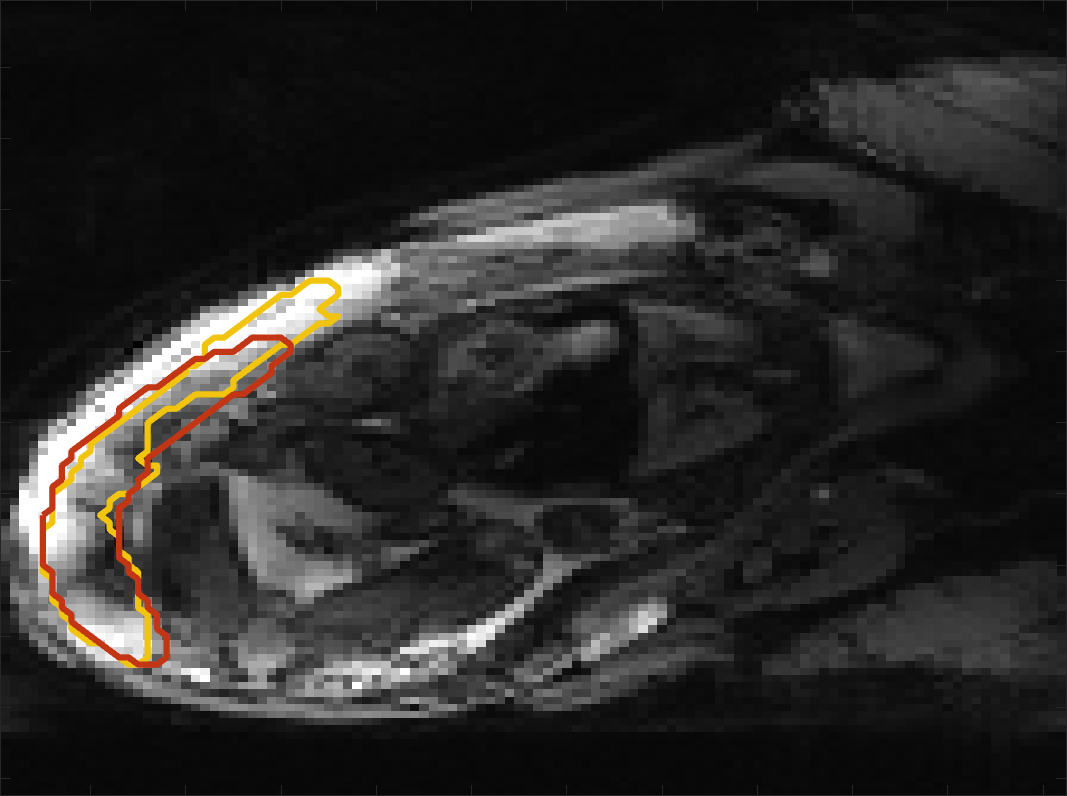

Figure 4 compares the predicted label maps with ground truth on subjects with increasing Dice scores using the BW-CE model. The model accurately identifies the location of the placenta, but in the worst cases misses boundary details.